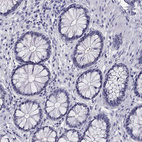

Immunohistochemistry analysis in human cerebral cortex and skeletal muscle tissues using HPA078302 antibody. Corresponding KCNJ10 RNA-seq data are presented for the same tissues.